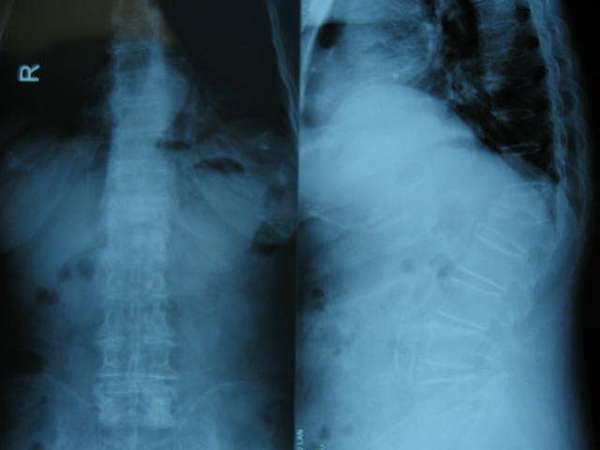

女性,69岁,腰背疼痛8个月,早期卧床2周后症状减轻,开始下地行走,虽然症状逐渐缓解但仍有反复加重,尤其是翻身、起坐、站立和行走时明显,平素多是卧床,摊扶上卫生间等,严重影响患者日常生活。查体发现患者胸腰段明显后凸畸形及压叩痛,活动明显受限,不愿起坐和站力。检查X片发现腰1、胸12两个椎体压缩骨折,MRI检查发现腰1骨折为陈旧性并已愈合,胸12骨折未愈合,有明显的渗出现象,是造成目前存在症状的原因。入院诊断:胸12压缩骨折,腰1压缩骨折(陈旧性)。

手术前X片---L1及T12均有压缩,且脊柱明显后凸畸形。